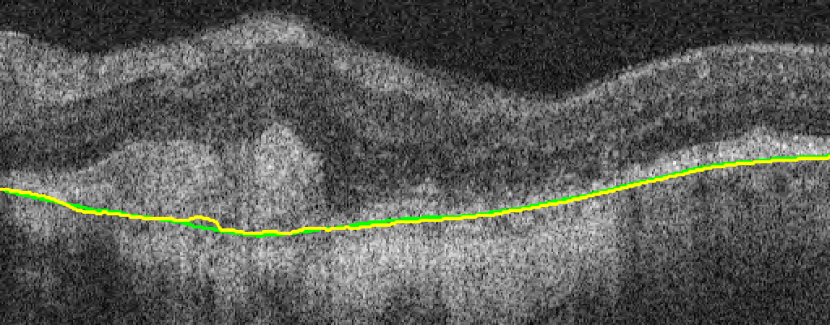

(a) Before TPS

(b) After TPS

A representative example of the influence of the curvature term is shown in Fig. 17. The proposed method with the help of the curvature term correctly finds the BM as opposed to Proposed w/o w/o TPS. The associated uncertainty is also adequately higher, signaling the lower confidence of the BM position estimate in this region. In contrast, the absence of leads to a poor uncertainty estimation in some incorrect segmentation regions.

(a)

(b)